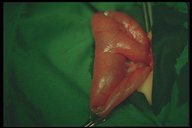

This Meckel's diverticulum is atypical one, it is identified on the mesenteric side whereas most diverticula are on the antimesenteric side

This Meckel's diverticulum is also atypical one with bifid appearance